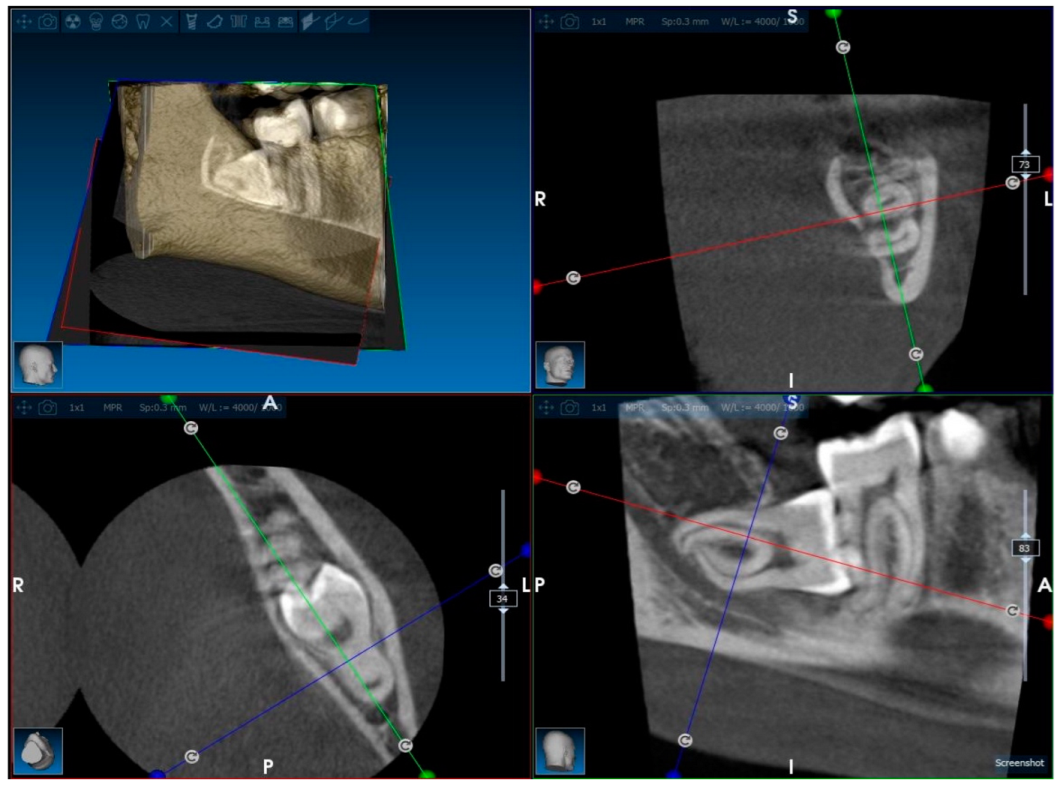

Orthopantomography (OPG) is the preferred imaging method for initial evaluation, offering a panoramic view of dental arches and adjacent structures (Figure 1). OPG combines low-radiation exposure with patient comfort. Computed tomography (CT) with specialized software may provide three-dimensional analyses for more complex cases (Figure 2).

Cone beam computed tomography (CBCT) offers enhanced diagnostic capabilities, particularly in evaluating the proximity of impacted molars to adjacent anatomical structures and predicting potential complications during and after surgery.

The choice of surgical technique and pre-extraction periodontal preparation must consider the patient’s clinical condition. Advanced periodontal surgical methods, such as guided tissue regeneration or use of biomaterials, may improve healing outcomes and reduce the risk of long-term defects. CBCT analysis plays a pivotal role in planning these interventions, offering precise evaluations of bone and soft tissue conditions.

The imaging modalities used, orthopantomography (OPG) and cone beam computed tomography (CBCT), represent standard practices for assessing third molar impactions and their associated periodontal impacts. OPG provides a convenient and low-radiation panoramic view, CBCT offers enhanced three-dimensional imaging crucial for evaluating anatomical proximity and predicting surgical complications. However, these methods have limitations, such as OPG’s two-dimensional representation and CBCT radiation exposure [30].

Figure 2. Cone beam CT scan of impacted third molar in different sections.